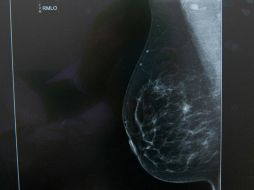

Suplementos Autoexploración de mamas, una técnica para vivir 15 de noviembre de 2013 - 11:25 hs UNAM Mujeres

Tecnología Molécula muestra rapidez de difusión del cáncer de mama 11 de noviembre de 2013 - 20:48 hs Descubrimientos ciencia Ciencia médica